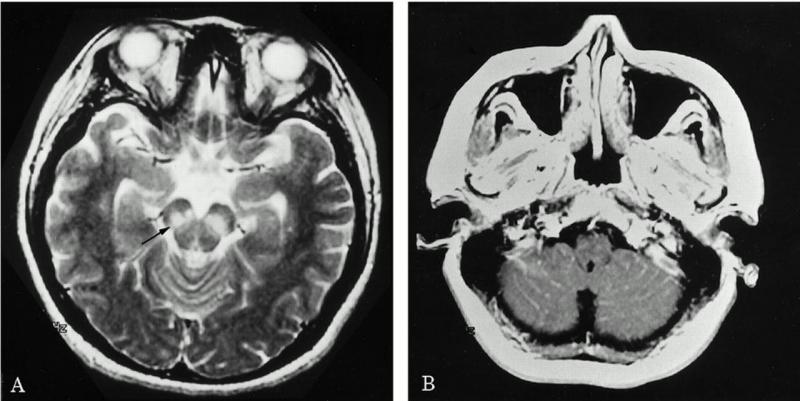

Uyku hastalığına yakalanan bir kişinin beyin tomografisi

Van Economo tarafından uyku hastalığından ölen birine yapılan bir otopside, insan beynindeki birçok işlevi engelleyen bir şişlik fark edildi.